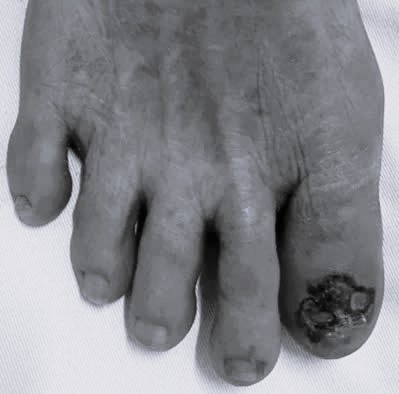

| Ung thư tế bào hắc tố kẽ ngón chân. Ảnh BVCC |

Ung thư tế bào hắc tố có thể biểu hiện ở mọi vị trí trên cơ thể. Tuy nhiên, ở người châu Á hay gặp ở lòng bàn tay - bàn chân, chiếm khoảng 50% các trường hợp.

Ngoài ra, thể ung thư tế bào hắc tố ở dưới móng, biểu hiện bằng các thương tổn tăng sắc tố không đều, chiếm một phần hay toàn bộ nền của móng cũng hay gặp.

Ung thư tế bào hắc tố dưới móng thường chẩn đoán muộn vì dễ nhầm với các bệnh khác như nốt ruồi dưới móng, xuất huyết do sang chấn, viêm quanh móng, nhiễm nấm, hạt cơm dưới móng.